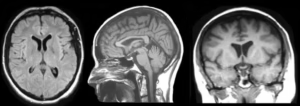

Neuroscience Perspective: Can Electromagnetic Energy Affect the Brain?

Neuroscience research confirms that electromagnetic fields can influence neural activity under specific laboratory conditions.

However, large-scale real-world neurological disruption through covert electromagnetic targeting remains scientifically unproven.